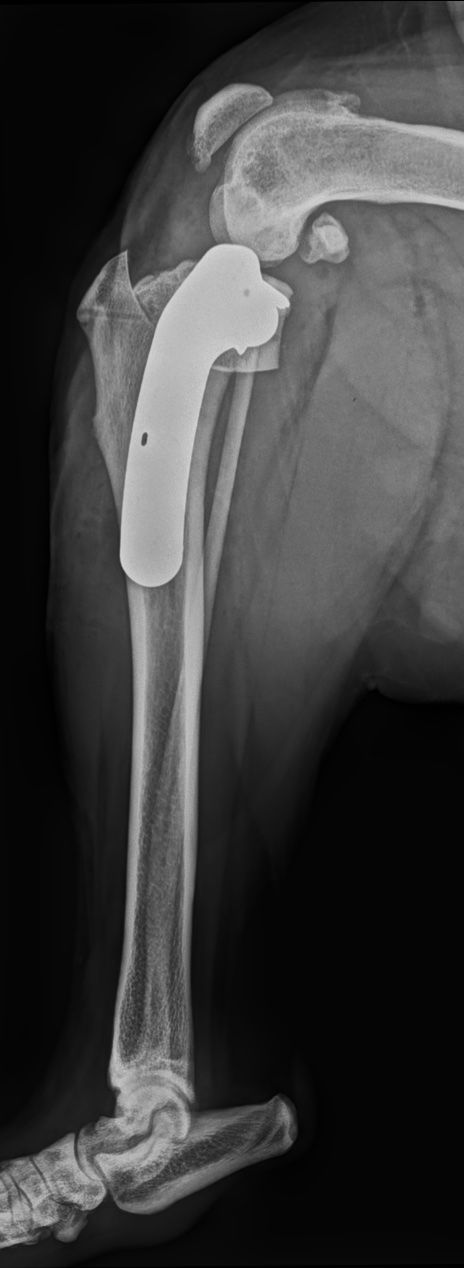

- Traumatologie & orthopédie : fractures complexes, lésions articulaires (coude/épaule/genou), évaluation pré-opératoire (TPLO, prothèse), suivi de consolidation.

La majorité des chirurgies orthopédiques nécessitent un bilan radiographique avant et après la chirurgie.